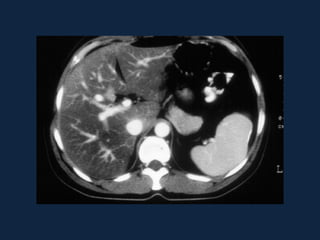

Abscessos Piogênicos

 Fase arterial         Fase portal

 Fase tardia

Abscessos Piogênicos  Fasearterial  Fase portal

Abscessos Piogênicos  Fase tardia